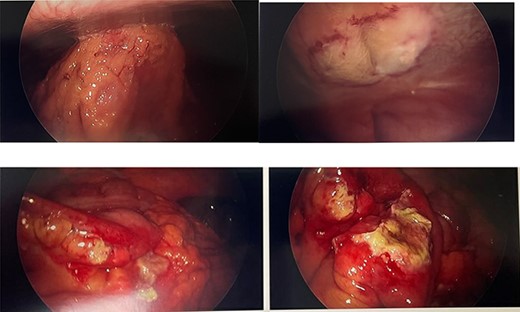

He presented to the emergency room with worsening lower abdominal pain for 1 week after undergoing bilateral ilioinguinal and iliohypogastric hot RF ablation with Pain Management. Per outside hospital, he underwent RF ablation at 80°Cfor 90 s. Computed tomography imaging was obtained which showed an inflamed area of small bowel with a localized area of pneumoperitoneum (Fig. 1). Given his normal vitals, lack of peritoneal findings on abdominal exam, and leukocytosis 14 000 with otherwise unremarkable lab work, we elected to initially treat with IV antibiotics, bowel rest and serial abdominal exams. On hospital Day 3, he was taken to the operating room for persistent pain and failure to improve. A diagnostic laparoscopy was performed. There was a scarred area on the peritoneum with adherent small bowel and omentum found. This single adhesion was taken down and the involved jejunal segment was inspected revealing a full-thickness perforation with surrounding erythematous bowel (Fig. 2). The intraoperative findings and timing post-RF ablation were consistent with delayed perforation secondary to jejunal thermal injury. A laparoscopic small bowel resection with intracorporeal stapled anastomosis was performed. His postoperative course was uneventful, and he was ultimately discharged post-op Day 3 after tolerating a diet and having bowel function.

Axial and coronal computed tomography scan views of the patient showing small area of pneumoperitoneum with surrounding small bowel inflammatory changes.